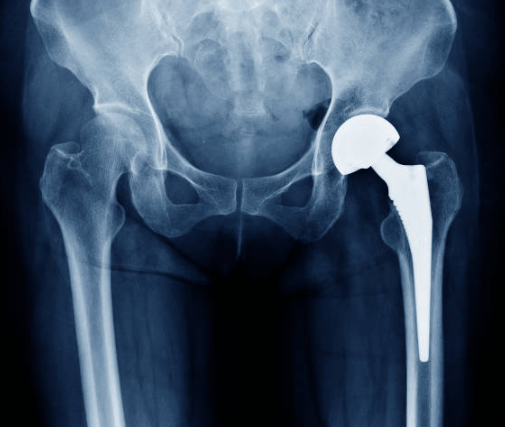

Back to the witch doctor, Vinnie. Xrays now the ticket were the path to more answers…or at least have a look inside, not much else. Confirmation, one sick hip, cartilage almost all gone.

Dr. Sergeo puts up the xrays. “And the Oscar goes to “Szpin’s RIGHT SIDE…starring NO CARTILAGE!” And Best Supporting role, “Szpin’s LEFT SIDE, SOME CARTILAGE REMAINS…”